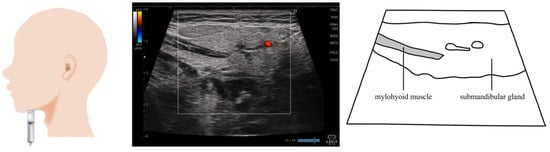

4. Mylohyoid Muscle (Figure 3)

| Mylohyoid thickness | Sitting position | Linear | Coronal plane | Measure the thickness of the mylohyoid muscle under the submandibular gland. |